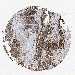

OVARIAN CANCER - Protein expressioni

A mouse-over function shows sample information and annotation data. Click on an image to view it in a full screen mode. Samples can be filtered based on level of antibody staining by selecting one or several of the following categories: high, medium, low and not detected. The assay and annotation is described here.

Note that samples used for immunohistochemistry by the Human Protein Atlas do not correspond to samples in the TCGA dataset.

Antibody stainingi

Antibody staining in the annotated cell types in the current human tissue is reported as not detected, low, medium, or high, based on conventional immunohistochemistry profiling in selected tissues. This score is based on the combination of the staining intensity and fraction of stained cells.

Each image is clickable and will lead to virtual microscopy that enables deeper exploration of all samples and also displays staining intensity scores, fraction scores and subcellular localization as well as patient and tissue information for each sample.

HPA030521

Cystadenocarcinoma, serous, NOS

Carcinoma, endometroid

Cystadenocarcinoma, mucinous, NOS

Carcinoma, NOS